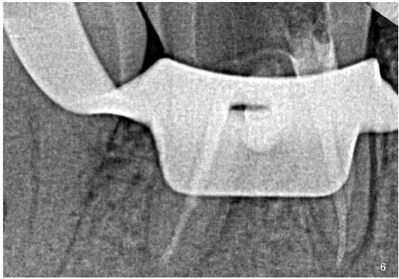

患者于一周后复诊(2021年3月23日),检查:46暂封完好,叩诊(-),无松动,根管内无异味及渗出,余未见明显异常。遂行"46根管充填治疗",46上橡皮障去暂封,去除富士Ⅸ玻璃离子后检查得iRoot-BP材料完善,无松动脱落,无明显缝隙,重新加盖富士Ⅸ玻璃离子,超声荡洗4根管,3%次氯酸钠冲洗,40#吸潮纸尖干燥,iRoot-SP根充糊剂+大锥度牙胶单尖法根充4个根管,X-ray示:46牙根管恰填(图6),富士Ⅸ玻璃离子垫底,松风F00流动树脂充填,调合,抛光。(操作视频于附件中)